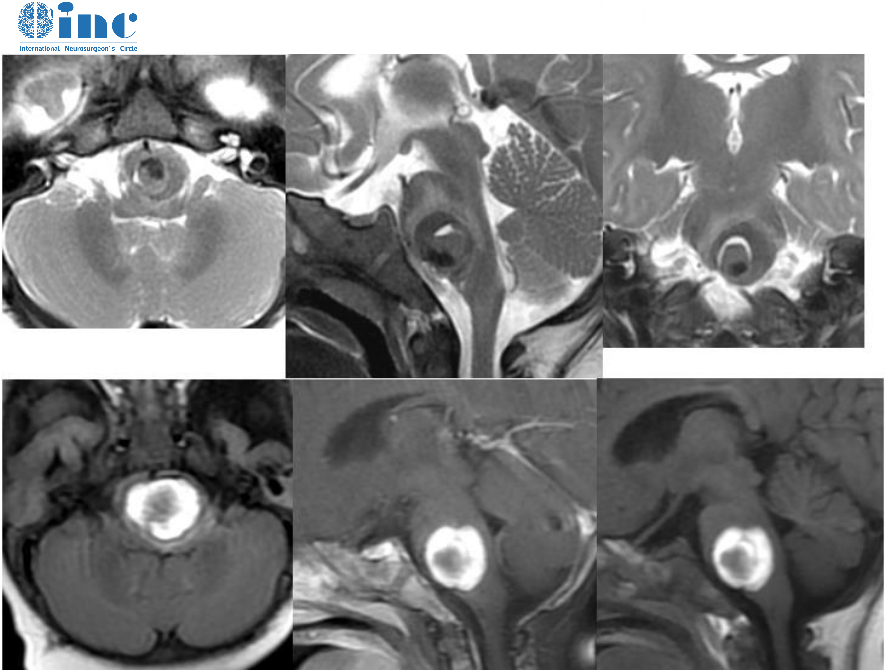

術后3個月時,巴教授給我做了隨訪——腫瘤已經完全切除,沒有異常的副作用,下一次復查時間為大約8個月后。這下,我真的可以安心了。

巴教授隨訪截圖